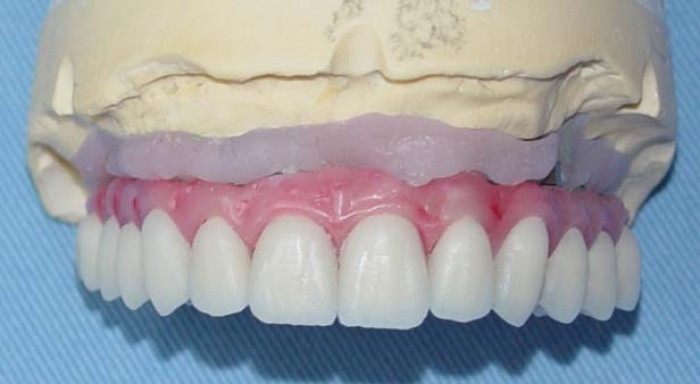

Prótese fixa de porcelana com dentes individuais

Imagens da prótese de porcelana com dentes individuais, ainda no laboratório